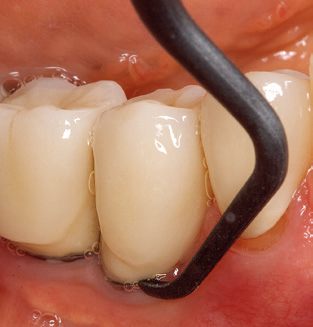

Good illumination of the working field facilitates the process considerably. The system used by the authors achieves this thanks to a 5x LED ring integrated in the handpiece. Naturally, a range of working tips for different indications is also offered. A straight, universally employable tip is the basic instrument required for machine cleaning of natural teeth (Fig. 5a and b). Curved tips, which allow access to exposed furcations, are also available for hard-to-reach areas in the posterior region (Fig. 6).

Of course, working tips for the cleaning of implant surfaces are also indispensable for SPT in patients fitted with implants. The implant cleaning attachment on the system used here is characterised by its tapered, hexagonal design. This design allows light, atraumatic penetration of the peri-implant pocket and displays a good cleaning performance (Fig. 7).

Fig. 4: Flexible probes with millimetre markings are recommended for the probing of dental implants (e.g. Colorvue Kit PCV11KIT6, Hu­Friedy). – Fig. 5a and b: A straight working tip (1P, W&H Dentalwerk Bürmoos GmbH) is a suitable instrument for use on all natural teeth. – Fig. 6: Curved working tips (3Pr/3Pl, W&H Dentalwerk Bürmoos GmbH) lend themselves to the processing of difficult-to-reach areas of the tooth and root surfaces (e.g. furcations). – Fig. 7: The tapered, hexagonal implant cleaning tip (1I, W&H Dentalwerk Bürmoos GmbH) permits atraumatic and efficient cleaning of the crown and abutment surfaces. – Fig. 8: Titanium and carbon curettes are suitable instruments for the manual cleaning of the implant surfaces.